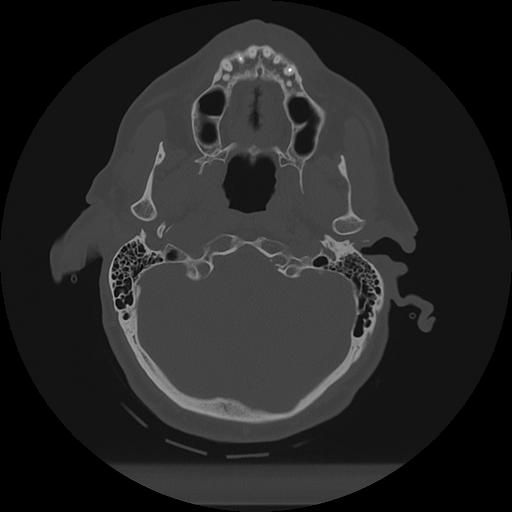

11 HUESO,,Axial,2.0,HUESO,,